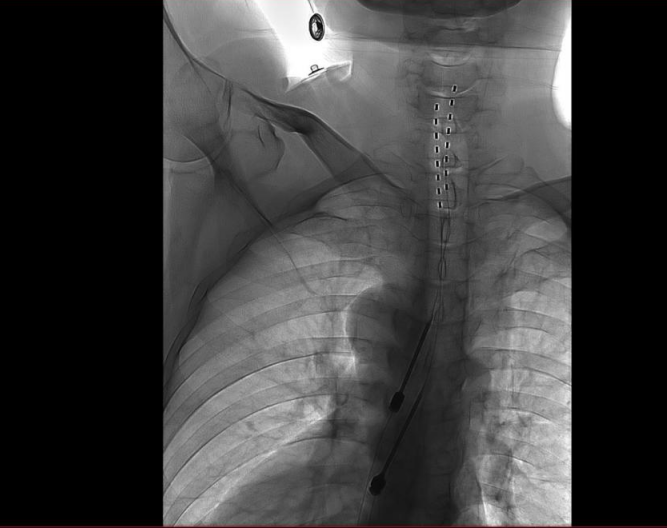

脊髓电刺激是一种通过将电极置入硬膜外腔,以低强度电流刺激脊髓后柱,抑制疼痛信号传导的神经调控技术,具有可逆性、微创性和可调控性等特点,已成为国际公认的治疗难治性神经病理性疼痛的重要手段。肖红主任医师团队通过局麻下经穿刺针将临时电极置入硬膜外腔,连接体外脉冲发生器。经测试,疼痛区域范围全覆盖,手术顺利完成。随后,通过术后每天记录疼痛改善程度及日常生活能力变化,廖先生的疼痛评分较前明显下降,镇痛效果明确。

从一期手术10天后电极被取出,到今年9月,廖先生疼痛又逐渐恢复至术前水平,既提示其疼痛具有持续性和难治性,又表明其对脊髓电刺激治疗反应良好,符合开展二期长时程脊髓电刺激植入术的指征。肖红主任医师表示,“相较于短时程一期测试治疗,长时程脊髓电刺激可实现持续的镇痛效果,患者可根据自身情况,通过遥控器自行调节,在提高镇痛效果的同时减少镇痛药物使用量,从而降低药物相关不良反应。”

经过神经外科、康复科等多学科团队充分评估与讨论,肖红主任医师团队为廖先生实施了二期长时程脊髓电刺激植入术。

手术通过微创硬膜外腔穿刺技术,于DSA(数字血管剪影造影)引导下将极细的电刺激电极与植入式脉冲发生器共同植入体内。

手术历经3小时,病人恢复良好。术后1周内,团队根据患者疼痛缓解及感觉区覆盖情况,对植入电极的刺激参数进行多次动态调控,目前廖先生疼痛明显减轻,预计可于近期顺利出院。